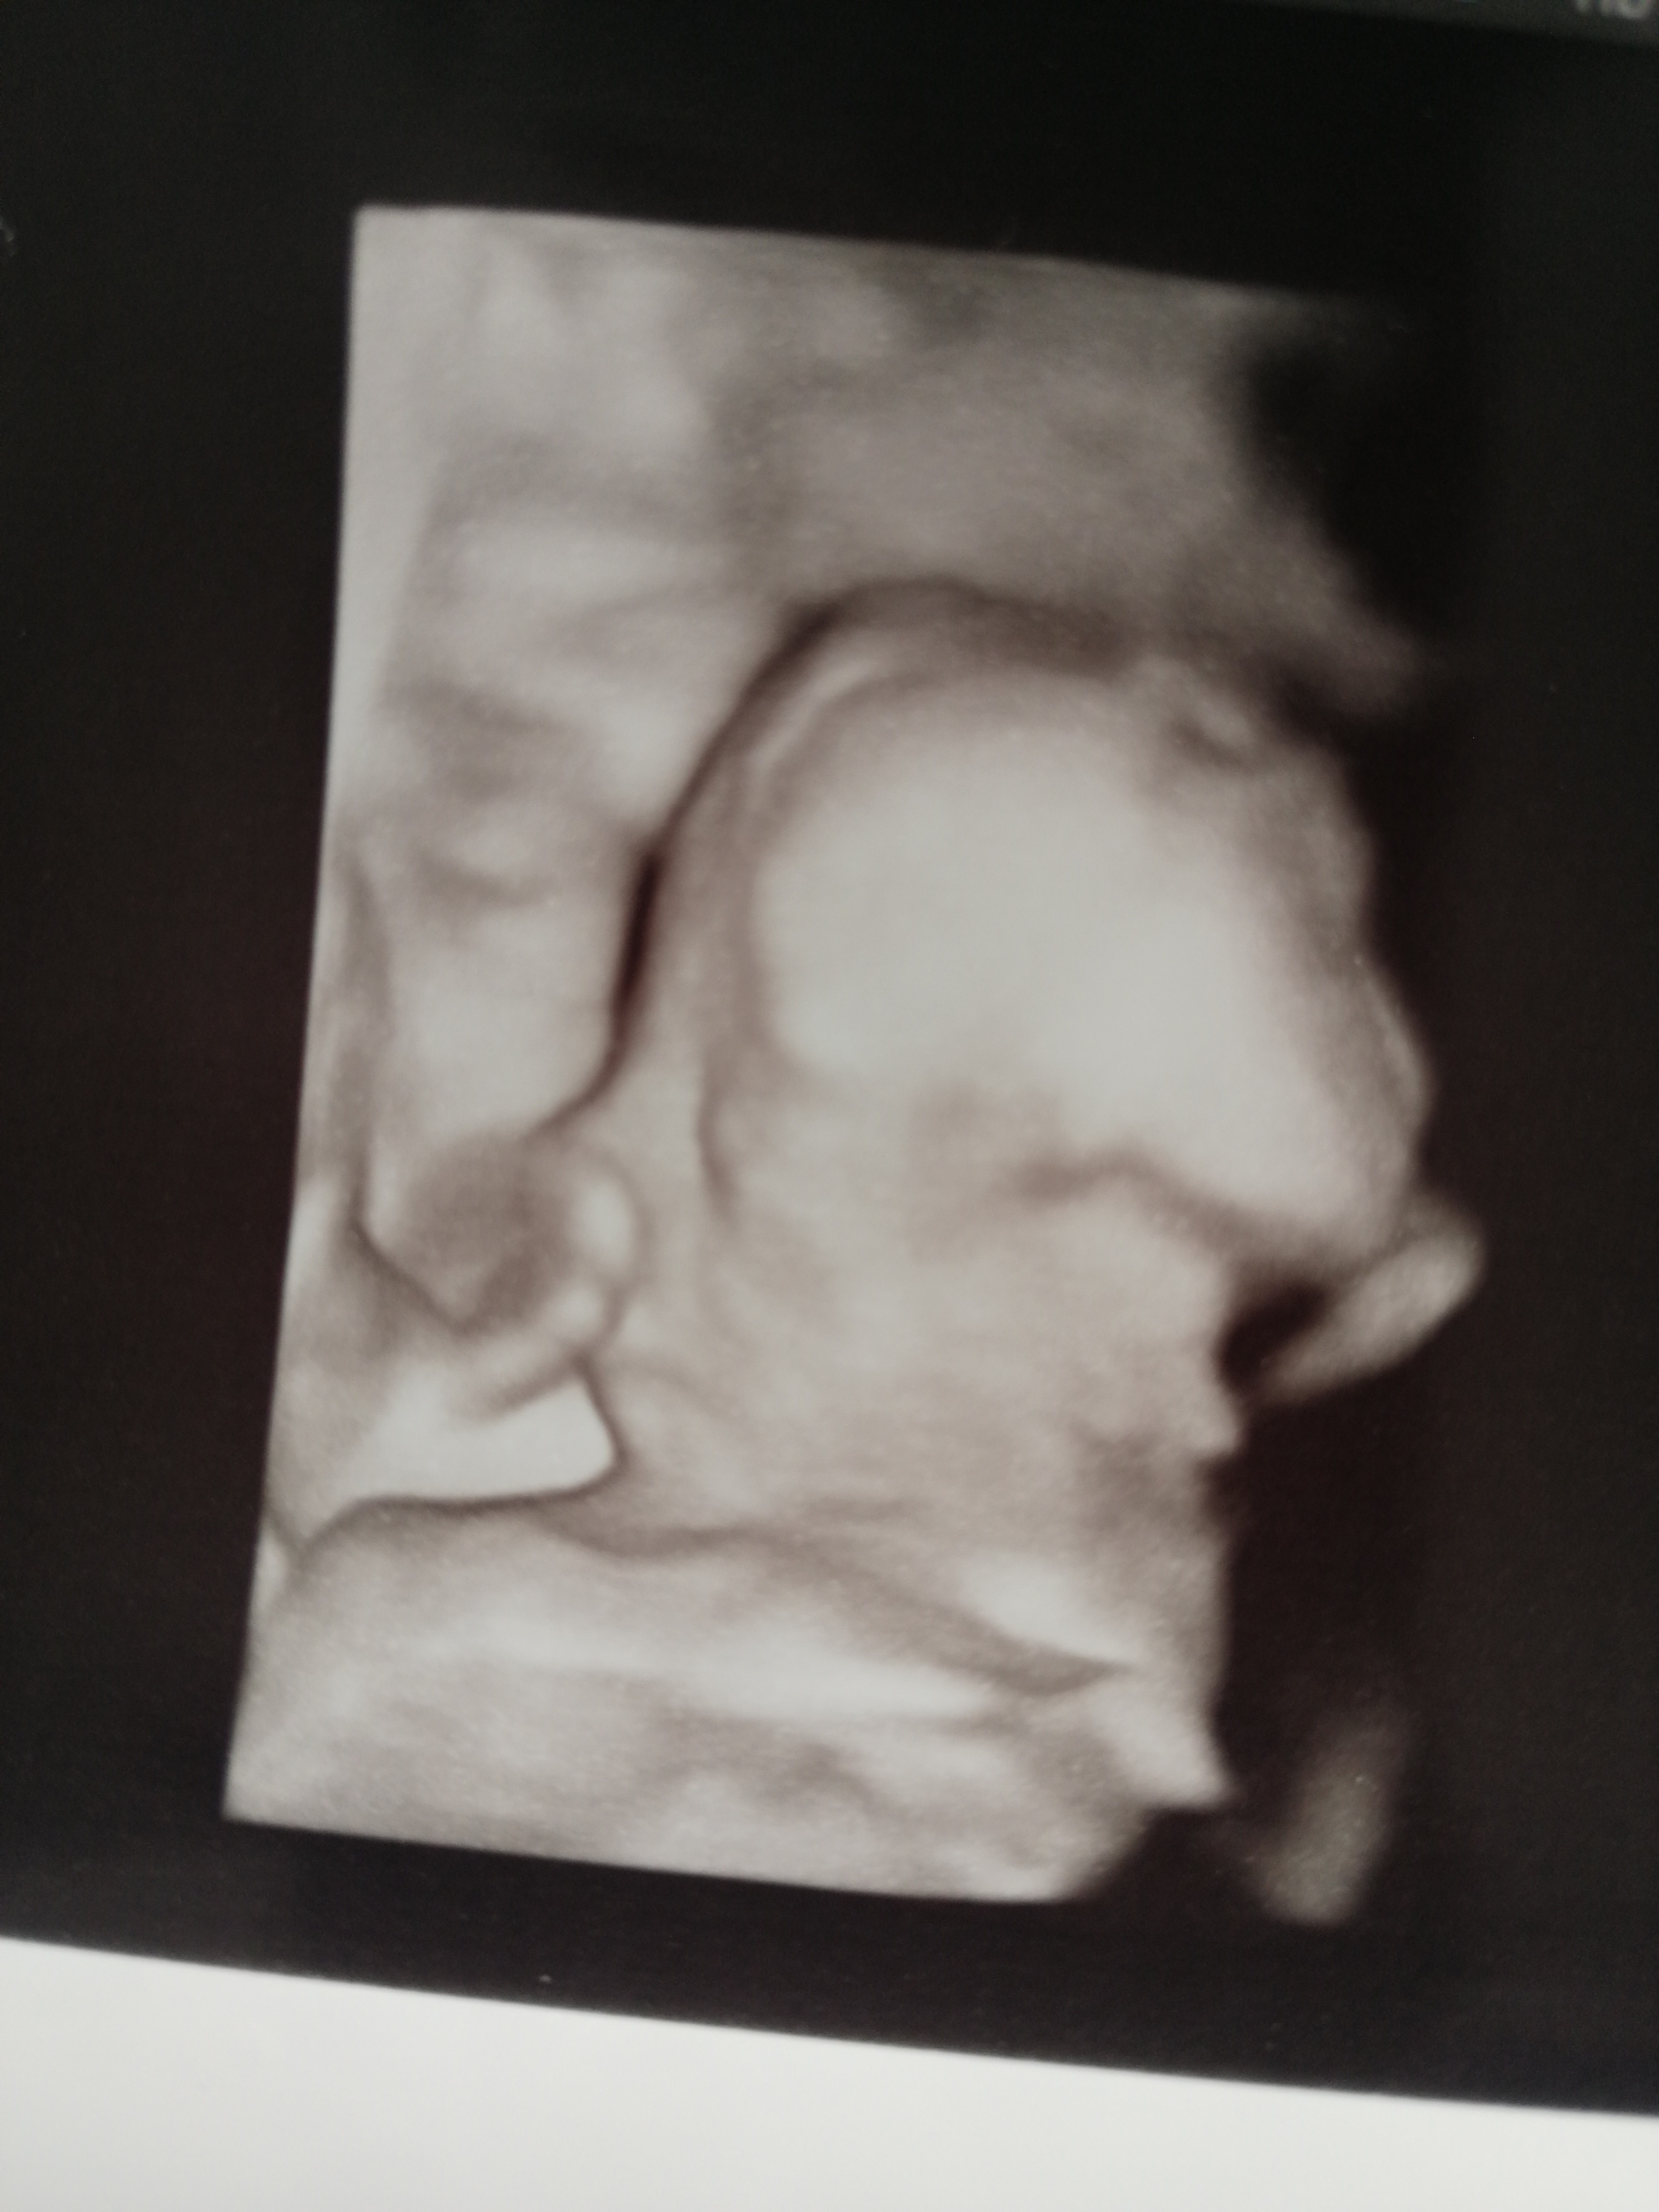

Hej, wczoraj byłam na wizycie, wiadomo już na 100%, że będzie chłopak, waży już 200g (17+2) 😄